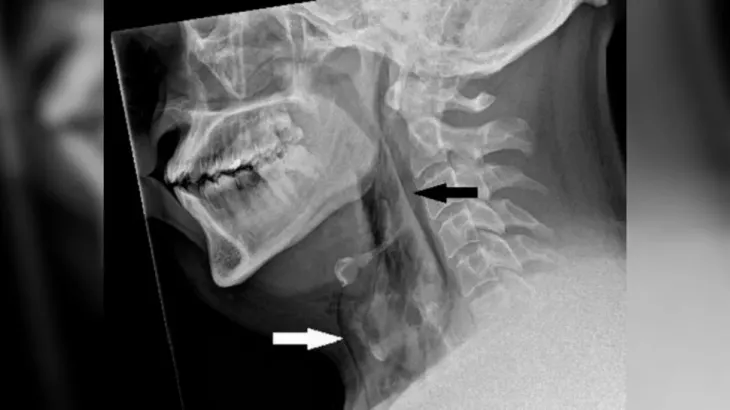

그는 호흡과 삼키기, 말하는 것에는 전혀 문제가 없었다. 의료진이 엑스레이(X-ray)를 촬영한 결과 피부 아래 가장 깊은 조직층 아래에 공기가 갇히는 질환인 폐기종의 징후를 발견했다.

CT 스캔 결과 A씨 목의 세번째와 네번째 뼈 사이에 찢어짐이 생겨 기도에서 공기가 빠져나와 목 조직과 폐 사이 공간으로 들어간 것으로 나타났다. 기도에 생긴 구멍의 크기는 지름 2㎜였다.